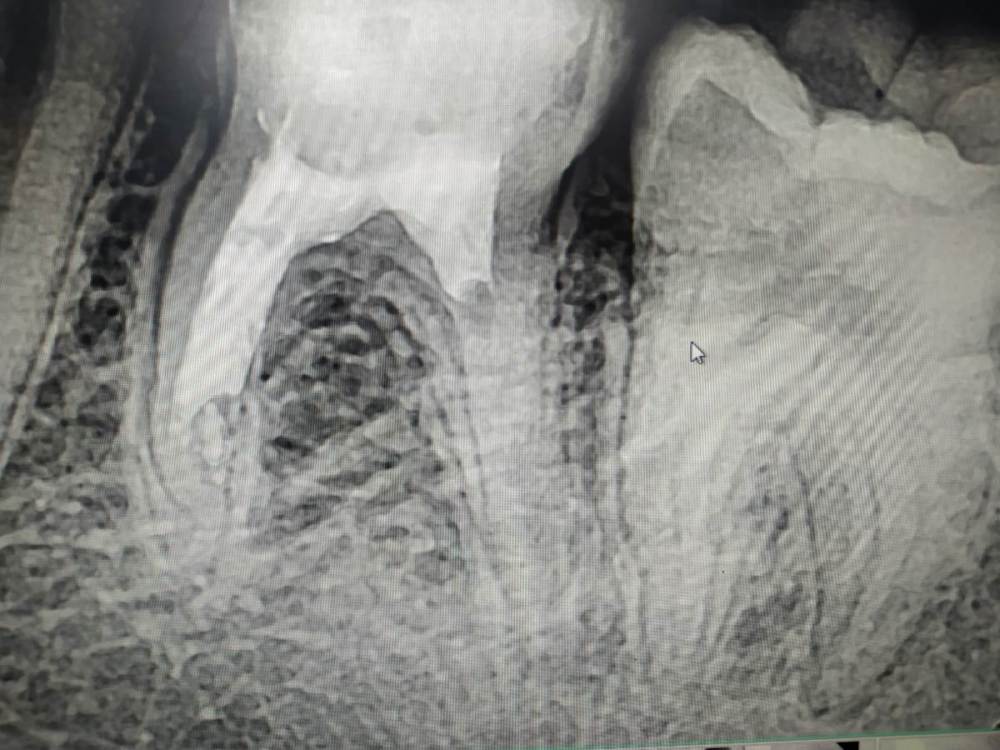

Первая резекция.

Внутриротовых фото нет, так как во время хирургии страшно, мир вокруг трясется или это я трясусь, поэтому не до фото.

Зуб 2.4, отломок в небном канале. До гайморовой рукой подать, ближайший лор в 200 км.

Жалобы: периодические боли при накусывании.

До:

1151819050_.thumb.png.c642dbc82dbfb554ac2baaf02a8b90b8.png

Сначала перелечиваем. Оба канала обработаны до 20.04, щечный прошел до конца, небный до отломка.

После моей эндодонтии:

363835048_.thumb.png.5b75eaaf360eb0fbb5879c69386c8ece.png

1943898502_.thumb.png.18347fcb26ec201fe8638f8f284b0a44.png

Резекция: на видосах у них как то все быстро, легко. Апексы в пустоте, пили не хочу. Померил расстояние до апексов, пошел. Разрез трапециевидный, откинул, выпилил окно шариком на прямом наконечнике. Убрал апекс щечного, чтобы долезть до небного. Слева клык, справа гайморова. Расширять окно боязно. Визуализировал небный апекс, благодаря отломку в нем. Спилюкал. Проверил сообщение, отрицательно. Углубления шариком в корнях, МТА. Готово. Поменять штаны и на рентген.

После резекции:

1813961350_.thumb.png.476564b527766e6d6e6f59cead471dcc.png